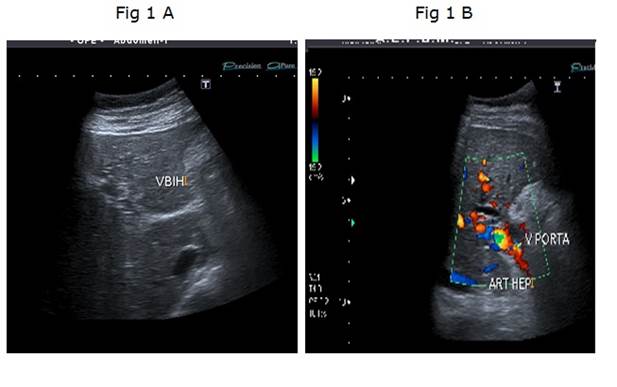

Mujer de 62 años, con antecedentes personales de hipotiroidismo, sin antecedentes de cirugía abdominal, con diagnóstico de síndrome de intestino irritable (episodios repetidos de dolor abdominal, sin síntomas atribuibles a la esfera hepatobiliar, con laboratorio, ecografía y endoscopias digestivas (alta y baja) normales). Consultó por un nuevo episodio de dolor abdominal de características clínicas similares pero con una bioquímica que mostraba una bilirrubina total de 0,62 mg/dl, fosfatasa alcalina de 509 U/l (20-240), gama-glutamil-transpeptidasa de 221 U/l (5-36), aspartato-transferasa de 95 U/l (5-27), alanino-transferasa de 125 U/l (5-33), con proteínas totales 7,30 g/dl, albúmina 4 g/dl, tasa de protrombina 72%, hemoglobina 12,1 g/dl (12,0-15,5), glóbulos blancos 7.9 mil/mm3 (4,3-10), plaquetas 331 mil/mm3 (130-440). La ecografía de abdomen (Figura 1a) mostró un hígado de forma y tamaño habitual, sin alteración de la ecogenicidad, de bordes regulares y sin lesiones focales. La vía biliar intrahepática presentaba leve dilatación y el colédoco proximal medía 9 mm. La vesícula biliar presentaba paredes engrosadas y se encontraba poco distendida a pesar del ayuno. El bazo medía 150 mm de longitud. En el estudio doppler (Figura 1b) no se identificó vena porta permeable, el hilio hepático presentaba varias estructuras vasculares algunas trombosadas, otras con calibre fino que correspondían a la transformación cavernomatosa de la vena porta. Las ramas portales intrahepáticas se encontraban permeables. La arteria hepática estaba aumentada de calibre y tortuosa al igual que sus ramas intrahepáticas. La colangioresonancia magnética mostró (Figura 2): estenosis de tercio medio de colédoco de una longitud aproximada de 2,5 cm, de bordes regulares, con dilatación proximal del colédoco, hilio y vía biliar intrahepática. No se observaba el cístico ni la vesícula biliar. El Wirsung no presentaba alteraciones. La videogastroscopía (VGC) informaba várices esofágicas grandes con puntos rojos que se extendían hacia el cardias y fondo gástrico (GOV-2). Las dosificaciones de CA 19-9 e IgG4 fueron 10,0 U/l (0,0-35) y 291 mg/dl (3,0-201), respectivamente. En la Tabla 1 se detallan los resultados de los estudios de la coagulación. La citometría de flujo en sangre periférica para el diagnóstico de hemoglobinuria paroxística nocturna no constató déficit de glucosil fosfatidil-inositol en las células sanguíneas (monocitos, eritrocitos, granulocitos).

En la imagen a la izquierda (Figura 1 A) se observa corte transversal en lóbulo izquierdo que muestra dilatación intrahepática de la vía biliar. En la imagen a la derecha (Figura 1 B) se observa un corte transversal a nivel del hilio hepático con doppler color que muestra desarrollo de colaterales en el hilio formando el cavernoma de la vena porta asociado a la dilatación y tortuosidad de la arteria hepática.